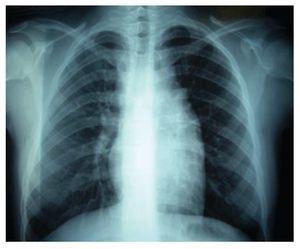

Por estas evidencias, se inició el tratamiento quimioterápico, con ciclos alternos de ciclofosfamida-vincristina-prednisona/doxorrubicinavinblastina-bleomicina-dacarbazina (COP/AVBD). Después del primer ciclo de quimioterapia, desaparecieron los síntomas generales, la adenopatía periférica y hubo disminución de la masa mediastinal; después de tres ciclos de tratamiento se observó persistencia del ensanchamiento mediastinal. Se optó entonces por aplicación de radioterapia en Mantle 25.2 Gy. En el monitoreo radiográfico posterior, se observó que aún perduraba el tumor mediastinal; razón por la que se le administraron dos ciclos más de COP/AVBD. Dado persístela persistencia de la misma imagen, se decidió cambiar el tratamiento a ifosfamida-carboplatino-etopósido (ICE) de tres ciclos. Por estudios radiográficos se observó una masa residual (Imagen 3), por lo que a la paciente se le realizó una toracotomía de exploración; con la que se localiza masa tímica, adherida al pericardio y grandes vasos; se tomó biopsia, que en el análisis histopatológico señaló timofibrolipoma. Por este dato, la decisión a la que llegó fue a la vigilancia de la evolución de la paciente. En la actualidad, su control con placas radiográficas ha revelado que la masa mediastinal permanece sin cambios y sin repercusión clínica evidente.

Imagen 3. Radiografía simple de tórax (de seguimiento) que muestra persistencia de un leve ensanchamiento mediastinal.